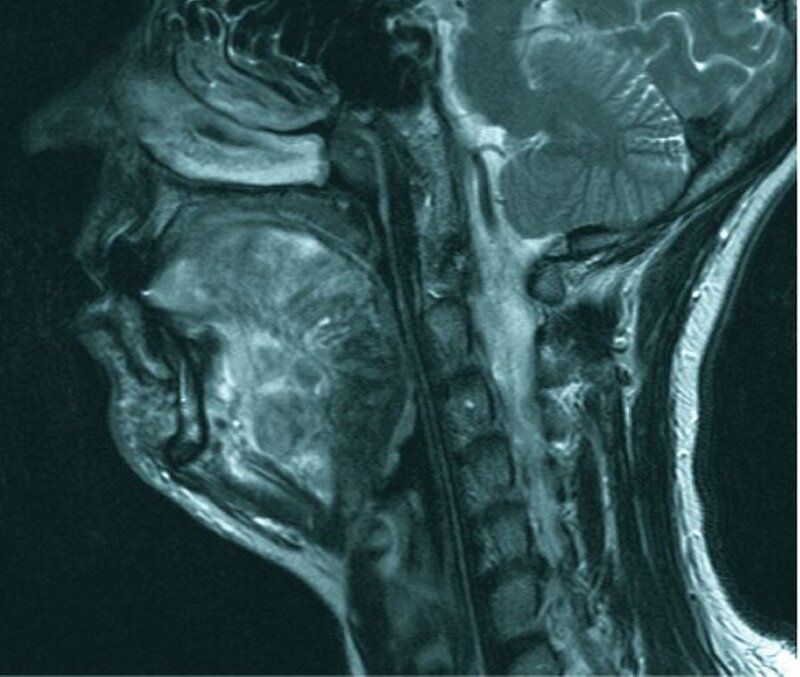

Die Magnetresonanztomografie (Ab-bildung 5) zeigte schließlich das gesamte Ausmaß einer weit ausgedehnten vaskulären Malformation, die große Teile der Zungenmuskulatur und des Zungengrundes durchsetzte. Die enorme Ausdehnung des Befunds mit Einengung des Atemweges im Zungengrundbereich stellte auch eine plausible Erklärung für die schwere Ausprägung des obstruktiven Schlafapnoe-Syndroms trotz fehlender typischer Risikofaktoren dar.